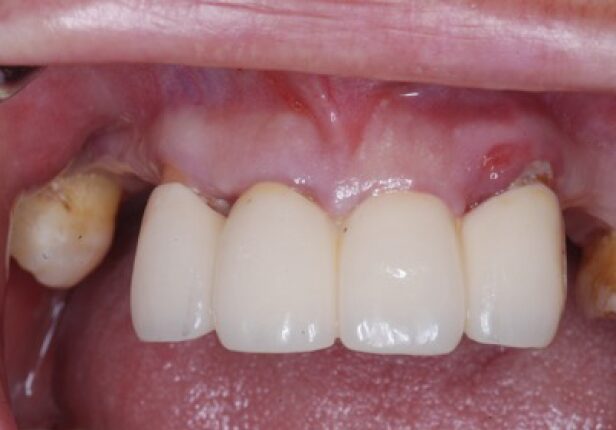

Maxilla Full Case Full case

Temporary Crown

Before Final Crown placement

Final Crown